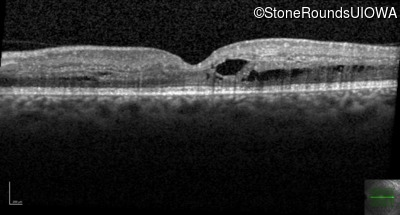

Optical Coherence Tomography - Right - Count Fingers 1'

Exemplar / OCT Stack

OCT Stack